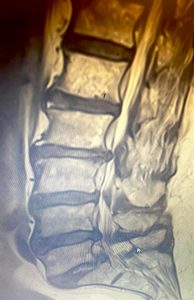

Erken teşhiste tedavinin daha başarılı sonuçlar verdiğini kaydeden Op. Dr. Serkan Zengin, “Uzun mesafe yürüme veya ayakta kalma ile bel ağrısı veya bacak ağrısı uyuşması gibi benzer belirtiler ortaya çıkabilir. Bu durumdaki hasta oturma, eğilme veya çömelme ile geçici bir rahatlama sağlayabilir. Belde kanal daralması tanısı hekimin alacağı hasta öyküsü fizik muayene ve röntgen tomografi veya mrg gibi radyolojik görüntüleme yöntemleri ile konulabilir. Tedavide ilaç ve takip yöntemleriyle hastalığın düzelme şansı oldukça yüksektir. Hastaların % 80'ine yakınında medikal ve fizik tedavi yöntemleri başarılı sonuç vermektedir. Burada erken teşhis, tedavi başarısını önemli ölçüde artırmaktadır. Erken evrede kas ağrısı, bel, boyun ve omurga hastalıklarında cerrahi müdahaleye gerek kalmadan büyük oranda tedavi edilebilmektedir. İleri düzeyde darlık ve şiddetli ağrısı olan hastalarda 3-6 aylık medikal tedaviye yanıt alınamadığı zaman cerrahi tedavi yöntemi uygulanabilir” ifadesini kullandı.

Operasyon hakkında bilgi veren Op. Dr. Serkan Zengin, “Cerrahi tedavide kişinin hastalık seviyesine göre bir operasyon planlanmaktadır. Farklı seviyelerde sıkışma ve kemik daralması varsa büyüyen kemik dokusu küçültülür, omurga kanal çapı genişletilerek sıkışan sinirlerin üzerindeki baskı azaltılır ve vidalarla omurga sabitlenir. Platin vidalar ameliyattan sonra 6 hafta süre içerisinde kemik ile kaynaşmaktadır. Böylece omurga taşıyıcı işlemine de devam edebilir. Ameliyattan sonra, genellikle hasta 2 gün içerisinde taburcu edilir. Operasyon sonrasında beli zorlayıcı hareketlerden ağır kaldırmaktan ve darbelerden hastanın kendini koruması gerekmektedir” dedi.